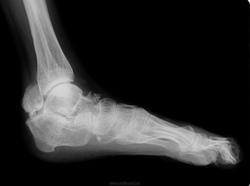

Заключение Главного детского хирурга ДЗ г.Москвы от 02.04.2007 года: Сирингомиелия. Патологический перелом Л2. Кифотическая деформация позвоночника. Радикуломиелопатический синдром. Врожденная сенсорная нейропатия с ангидрозом и спонтанным ангиолизисом. Вальгусная деформация правого коленного сустава на почве остеолизиса дистального мыщелка бедренной кости, нестабильность коленного сустава справа. Плоско-вальгусные стопы.

В неврологическом статусе: Сознание ясное, контактна, ориентирована. Менингеальных знаков нет. Умеренное когнитивное снижение. Несколько эйфорична. Речь дизартричная (неправильный прикус). ЧМН: без патологии. Парезов не определяется. Сухожильные и периостальные рефлексы с рук низкие, без разницы сторон. Коленные и ахилловые отсутствуют. Четких чувствительных нарушений не выявлено. Гипотрофия мышц верхних и нижних конечностей, ягодиц. Грубая деформация правого коленного сустава с формированием ложного сустава, отведением правой голени кнаружи под углом 30-40 град, деформация костей стоп, эквинус с 2-х сторон. Укорочение правой ноги на 15см. ходит с опорой на «мыски». Кифоз шейного отдела. Грубый кифоз поясничного отдела с формированием горба. Сколиоз. Мышечный тонус в верхних конечностях не изменен, в нижних конечностях сни жен, больше справа. Гипермобильность в правом тазобедренном суставе. Тазовые функции: не нарушены.